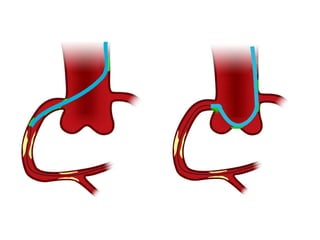

Extension ↑↑ force transmission

Shape modification Deep intubation          ↑↑ Force

↑ contact aorta    ↑ contact coronary    transmission

bypass tortuousity

Improved coaxial

Amplatzing                           alignment

only

•  2cm intubation equates to 8F guide   Takahashi CCI 2004

Extension ↑↑ forcetransmission Shape modification Deep intubation ↑↑ Force ↑ contact aorta ↑ contact coronary transmission bypass tortuousity Improved coaxial Amplatzing alignment

only only •  2cm intubation equates to 8F guide Takahashi CCI 2004